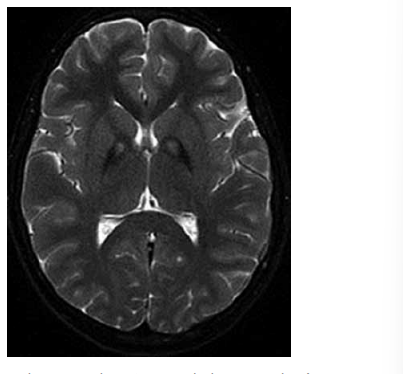

Adolescente de 13 anos de idade é trazido ao pronto-socorro por episódio de queda da bicicleta com traumatismo da região lateral da cabeça. Inicialmente, ele se apresentava alerta, porém, após 25 minutos do acidente, evoluiu com diminuição do nível de consciência. Tomografia de crânio sem contraste realizada na urgência demonstra o achado a seguir.

A estrutura vascular mais provavelmente acometida neste quadro é: